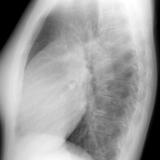

ASD 1 Lat